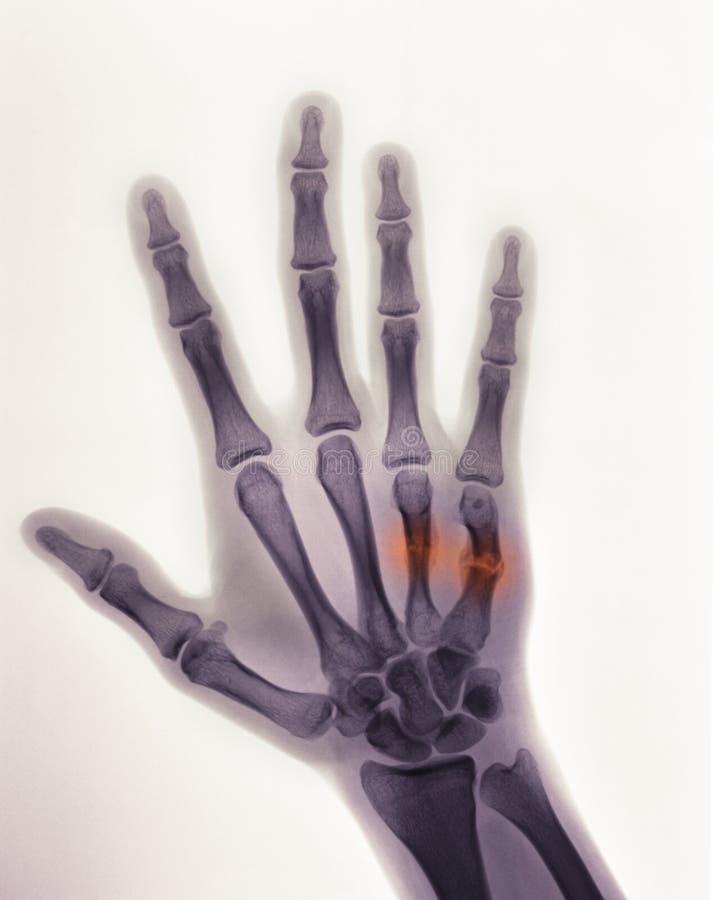

Hand Xray Showing a Boxer S Fracture Stock Photo Image of xray X Ray Boxer's Fracture Treatment varies depending on whether. a boxer's fracture, or metacarpal fracture, is a bone fracture that affects knuckles in the hand. fracture of the 4th or 5th metacarpal caused by an axial load, typically from punching a person or object; Treatment varies depending on how far out of place. Causes include punching or smacking. Pain or swelling along. X Ray Boxer's Fracture.